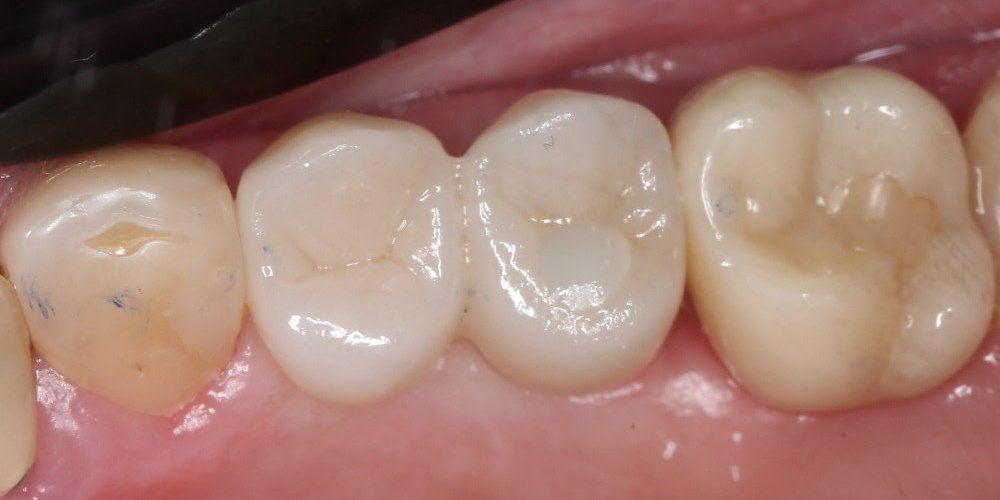

Имплантация жевательных зубов,

это самая востребованная операция.

Анна Анатольевна Кушнарева

хирург - имплантолог

фото коронок